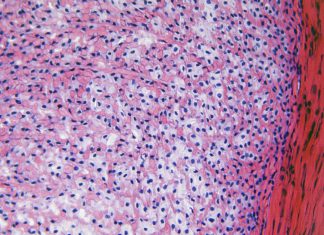

Stukjes gewricht uit de diepvries

In het laboratorium van de afdeling experimentele reumatologie van het Nijmeegse Radboudumc is zojuist knieweefsel binnengebracht van een patiënt bij wie deze middag de...